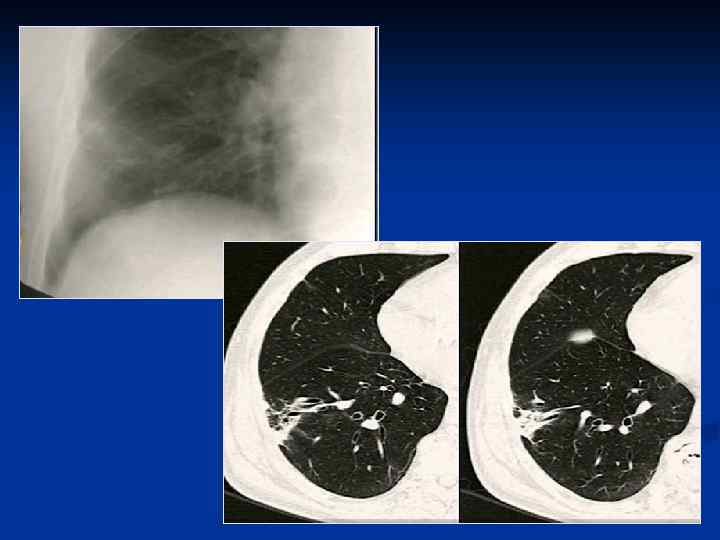

ПН язычковых сегментов Постепенное рассасывание ПН Формировние пневмосклероза

Бронхопневмония Локальный характер изменений (1 -2 сегмента) Перибронхиальные, центрилобулярные очаги или небольшие инфильтраты Субплевральное расположение очагов Контуры очагов достаточно четкие Денситометрическая плотность - +20…+40 HU Просвет бронхов свободен, стенки утолщены, в процесс вовлечены бронхи 5 -7 порядка

Пневмония S 6 левого легкого

Протокол - в S 6 левого легкого выявляется инфильтрация легочной ткани смешанного характера, на фоне которой прослеживаются просанты бронхов, занимающая сегмент, контактирующая с плеврой - усилен сосудистый рисунок в правом легком - утолщена плевра по ходу косой междодевой щели - корни реактивны - диафрагма расположена обычно Заключение: Рентгенологические признаки пневмонии S 6 левого легкого